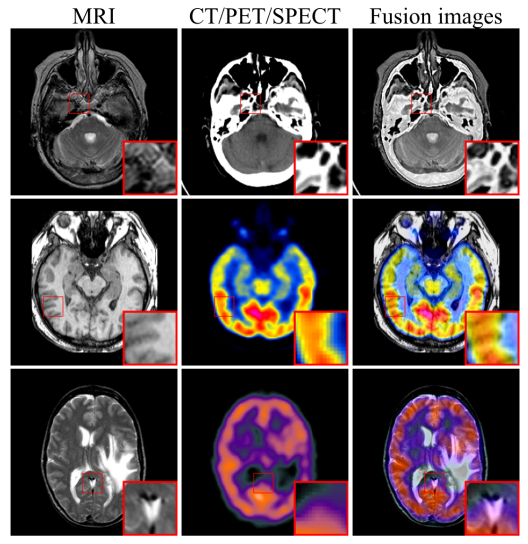

医学影像是临床诊断的重要手段,由于解剖结构影像和功能影像的成像原理不同,单模态医学影像的信息存在着局限性。通过图像融合技术将不同模态的医学影像融合在一起,实现不同模态间互补信息和突显优势,增强影像信息量,有助于更准确诊断和有效治疗。

基于卷积神经网络的深度学习方法因其强大的建模能力而被应用于图像融合,但其感受野的局部性限制了融合性能的提升。为解决这个问题,张小志课题组提出一种全新的无监督多模态医学影像融合框架,设计了一个联合Swin Transformer和卷积神经网络模块对多尺度医学影像特征进行融合,该模块由一个用于捕获全局上下文信息的残差Swin Transformer分支和一个用于捕获局部细粒度信息的卷积神经网络分支组成。

此外,为进一步有效地保留医学影像的纹理特征和强度信息,定义了包含内容损失和强度损失的联合损失函数来约束融合模块,并引入自适应权重来控制源图像的信息保留程度。所提出的框架在CT-MRI、PET-MRI和SPECT-MRI等多个融合任务上进行实验,通过定性和定量分析验证了模型的优越性。